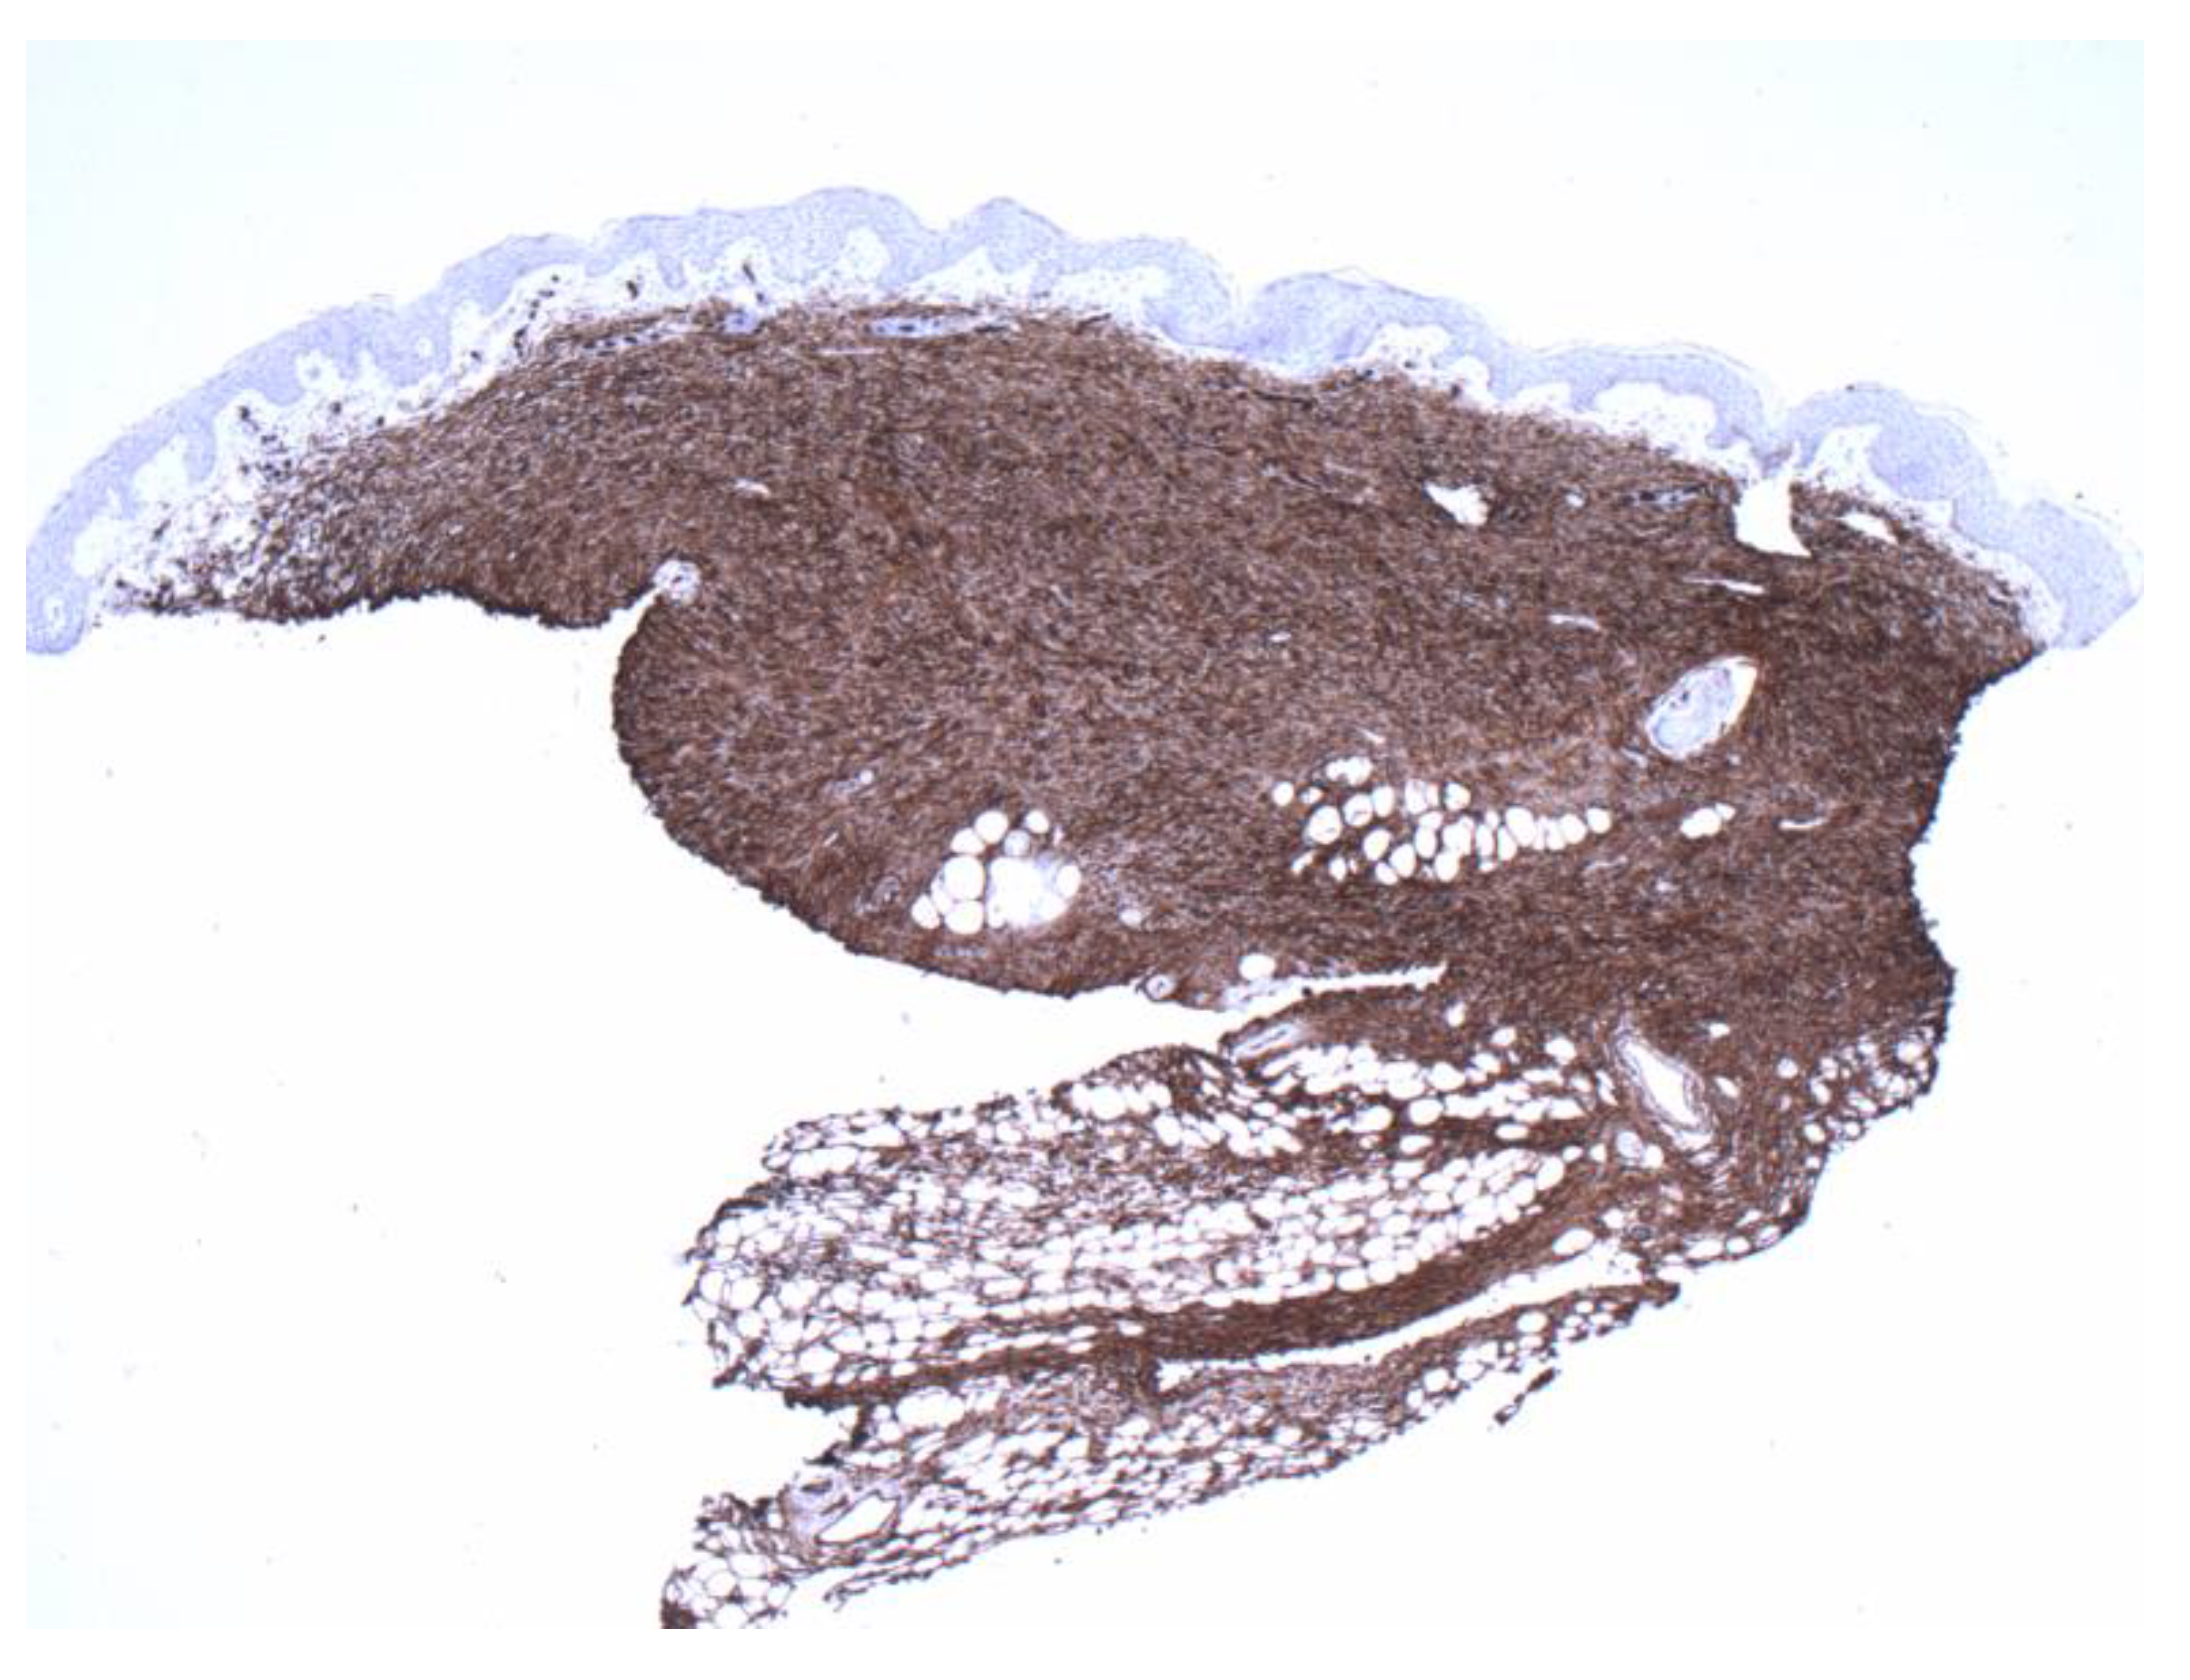

Figure 4.

Positive CD34 staining with contrasting sparse-superficial and dense-deeper areas (4×).

Figure 6.

Diffuse and even staining was also highlighted by CD34 preparation, compared with Figure 4. (4×).